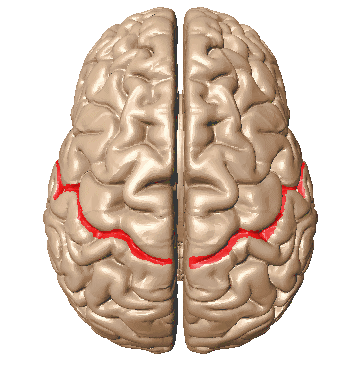

The incisura preoccipitalis cuts into the upper convexity of the brain hemispheres. As a result, the gyrus postcentralis, in which there are sensory centers, belongs to the parietal lobe. There are two curves in the lower area of the parietal lobes. Those are the anterior, gyrus supramarginalis and posterior, gyrus angularis.

Now, we will elaborate on anatomical parts of the parietal lobe about their specific functions. First of all, the postcentral gyrus of the parietal lobe (the primary somatosensory region) processes somatic sensory stimuli that serve to recognize the shape, composition, and weight of an object.

The spatial organization center also applies to the primary somatosensory cortex located in the anterior portions of the parietal lobe. The somatosensory functions of one side of the body are controlled by the contralateral hemisphere of the brain.

空间组织中心位于顶叶前部的初级躯体感觉皮层。身体一侧的躯体感觉功能由大脑的对侧半球控制。

Furthermore, the posterior central gyrus houses the centers of sensitivity are projected with a projection of the body similar to that of the anterior central gyrus. A human face is projected in the lower third of the gyrus. The middle third segment projects a hand, while the foot is projected in the upper third part.

In the upper parietal gyrus, there are centers in charge of complex types of deep sensitivity: musculoskeletal, two-dimensional spatial sensation, sense of weight and volume of movement, sense of object recognition to the touch. The posterior to upper portions of the posterior central gyrus contain localized centers, providing the ability to identify one’s body, its parts, their proportions, and their relative position.

The most important sensory area is the parietal cortex segment of the postcentral gyrus. In addition, its corresponding part of the paracentral lobe plays a very important sensory role. These zones are called somatosensory region I.

In addition to the somatosensory region I, there is a smaller size region called the somatosensory area II, located at the intersection of the central sulcus with the upper edge of the temporal lobe, at the depth of the lateral sulcus. The degree of localization of body parts is less pronounced.